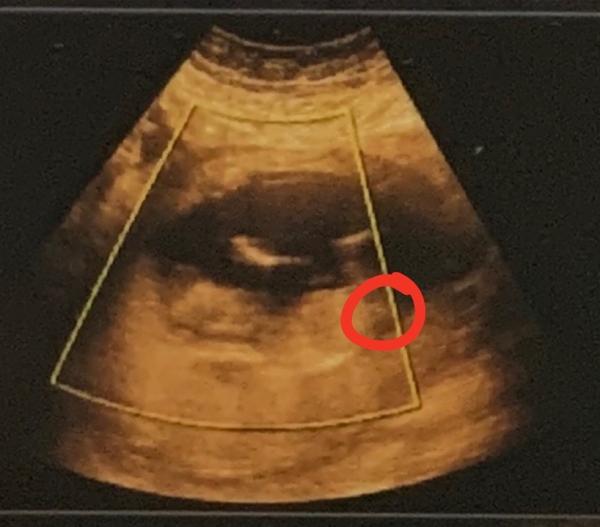

Je to holčička nebo chlapeček? Foto ultrazvuku

Ahoj maminky a budoucí maminky 😉 Prosím, poradila byste mi některá, co vidíte na fotce z ultrazvuku ve 20. týdnu za pohlaví? Určitě jste foteček viděly už mraky, proto vás žádám o radu...Nechci nikoho ovlivnit, proto svůj tip řeknu později 🙂 Děkuju moc!!!

@sebinka123 Hodně jsem to zkoumala a klidne bych tipla holku... Ono 13+1 je celkem dost a tam uz ten chlapeček bývá lépe vidět ;)

@sebinka123 na té poslední 2D fotce vidím holku 💃 na 13. týden si myslím, že by to mohla být spíš holka 🙂 4D fotky nejsou na upřesnění pohlaví dobré

@sebinka123 Já si myslím, že u Vás ten hrbolek je holčičí, na ten týden, kdy jste byla, by byl kluk víc nahoru a šikmý. Z té fotky, kde to vidím, miminko sice neleží úplně rovně, ale já si myslím, že to bude holka. My jsme vydrželi si neříct i u druhého, někdy to jsou nervy :D Ale při porodu to je pak zážitek 🙂 Já něco poznám z ultrazvuku, ale dokud to není oficiálně od dr., tak to beru jen jako můj tip ;) K tomu na tom ultrazvuku je to rychlé a vidíte jen chvilku něco, oproti fotkám, které máte v ruce a můžete zkoumat 🙂 Jinak já tohle těhu mám po tom 3. měsíci jiné, předtím mi bylo špatně jako s kluky, ale myslím, že to bylo teď méně a těhu nevolnosti už netrvají, kdežto s kluky ano a musela jsem furt jíst. Ale na tohle já moc nevěřím. My jsme třetí chtěli, i kdyby předtím byl páreček, ale teď by ta holka teda byla super :D

@sebinka123 Nevim... Nějak mám pocit i podle tvaru hlavičky, ze to bude spis holcicka 😂. Ale opravdu to berte jenom jako nějaké moje tušení/intuici. Oni ty snímky mohou často zkreslovat! Každopádně držím palce, ať to bude, co to bude 😘.

@sebinka123 ale fakt to není jisté, vyloženě pindoura tam nevidím, tady bych řekla jen tak na 65 % kluk ale pokud mi řeknete hodnotu hcg tak si budu jistější